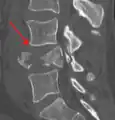

A burst fracture of L4 as seen on CT -

A burst fracture of L4 as seen on CT